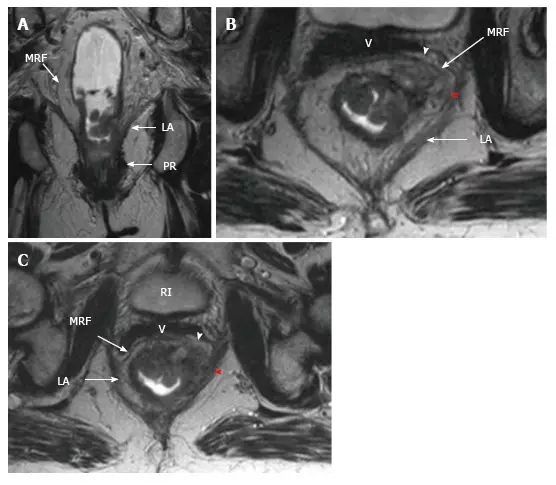

5. 低位肿瘤 T 分期

表 1 和图 14、图 15 显示了如何鉴别肿瘤 T 分期和环周切缘(CRM)。

图 15. Ⅳ 期低位直肠癌。

在 T2 加权(A)冠状面(B,C)轴向磁共振图像显示,直肠癌浸润提肌(红色箭头)和直肠系膜筋膜(白色箭头)。

LA:肛提肌;PR:耻骨直肠肌;MRF:直肠系膜筋膜;BL:膀胱;V:阴道。